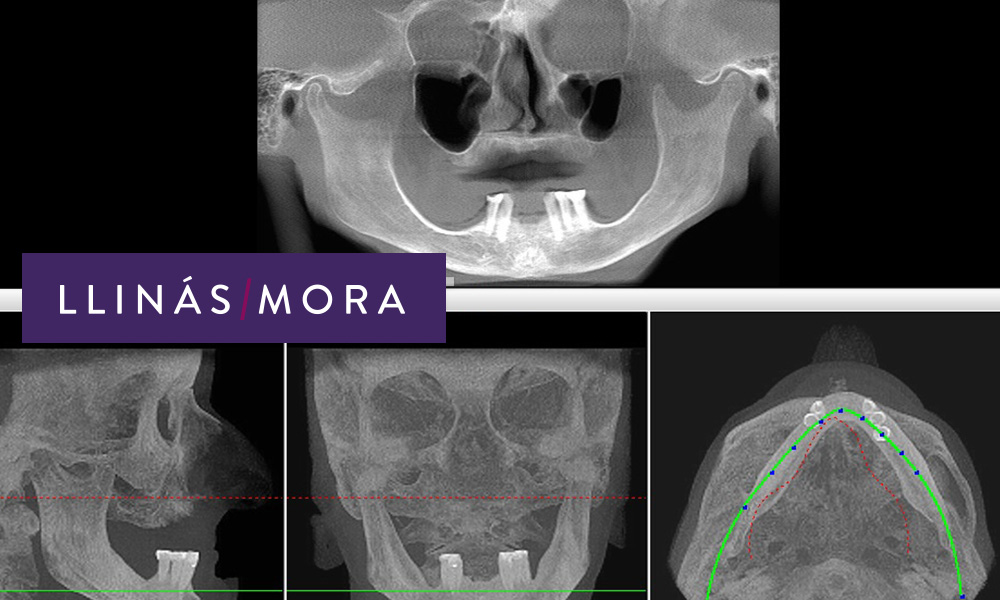

1. TAC INICIAL. PERDIDA OSEA MUY AVANZADA. Paciente mayor de 70 años portadora de dentaduras postizas de hace muchos años.